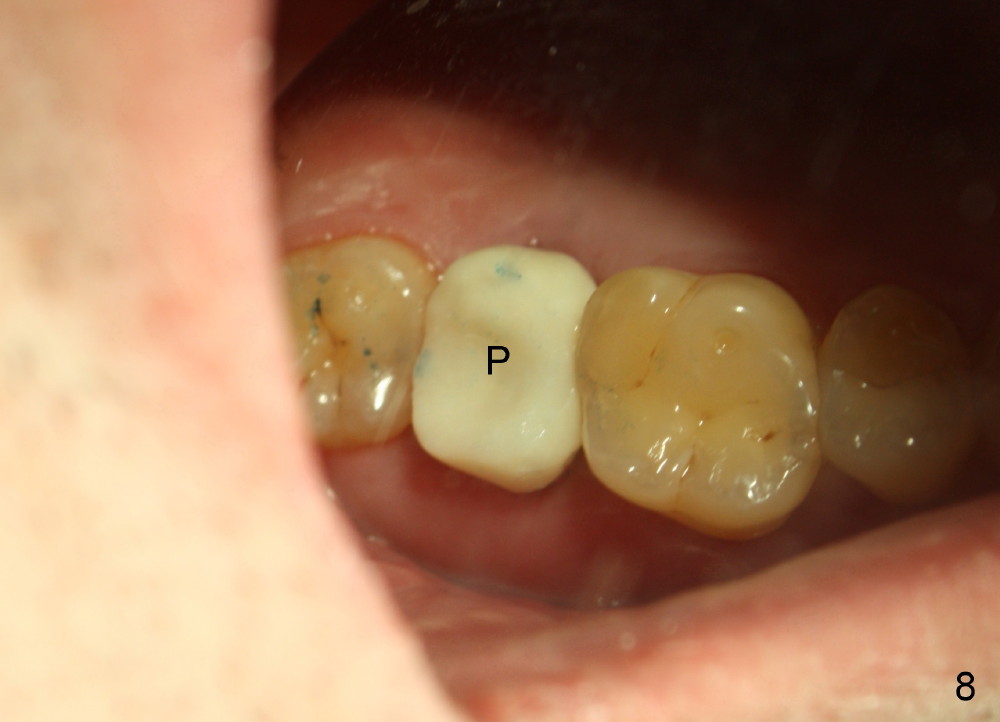

To prevent the narrow spaces from getting worse during osteointegration, an immediate provisional is to be fabricated. There is not enough occlusal clearance when the abutment is reduced ~1.5 mm. The abutment is removed; the implant is placed ~ 1 mm deeper with primary stability. Then the occlusal clearance is sufficient; the provisional is made. Mixture of autogenous bone, allograft and Osteogen is placed in the remaining buccal and lingual sockets (Fig.7 *). The provisional is temporarily cemented (Fig.8 P), which keeps the bone graft in place.